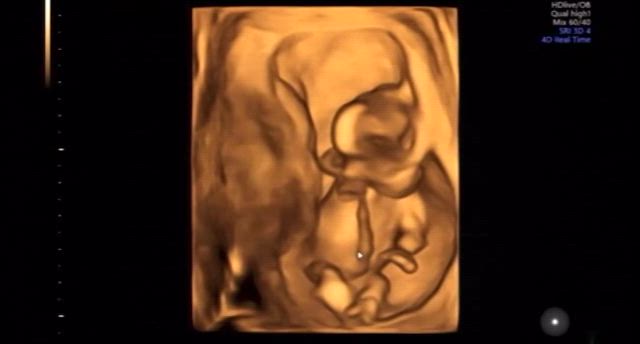

【12w6d】エコーで見えた我が子の癖(動画有)